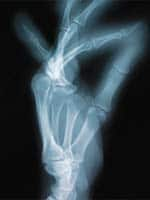

Standard medical advice for people with osteoporosis is to take a calcium supplement with vitamin D, and often a bisphosphonate drug such as Fosamax® or Actonel®. Even with this advice, incidences of osteoporosis are soaring. Aging adults continue to suffer lethal fractures and diminished bone strength. Unfortunately, standard medical advice alone might not be sufficient to stem the devastating erosion of bone mass that accompanies normal aging. In treating osteoporosis, many doctors have overlooked one of the most critical components for supporting healthy bone matrix: the trace mineral boron. Without boron, the absorption of calcium can be limited and often underutilized.1 Researchers have concluded that boron is an essential factor in facilitating the bone-building effects of key nutrients such as calcium, magnesium, and vitamin D. Numerous studies demonstrate boron is critical to maintaining and improving one’s bone health.1 Healthy bones, however, are just the beginning of the boron story. In this article, we examine boron’s many health-promoting effects, which also include relieving joint pain associated with arthritis, reducing the risk of prostate cancer, preserving cognitive function, and relieving oxidative stress. Further, we examine how you can ensure that you are benefiting from the most advanced, bioavailable boron formulation available today. Boron: An Often-Deficient MineralBoron is a trace mineral that is essential to plant growth and in turn finds its way into the human diet. Boron is present in plant foods such as fruits (especially plums, grapes, and avocados), vegetables, nuts, and legumes. Despite its availability in nature, ingesting adequate amounts of boron can be difficult. For one thing, boron levels in plant foods are rather low.2 Moreover, modern dietary habits almost ensure boron deficiency, as many people do not eat nearly enough fruits and vegetables. In the United States, estimated daily boron intake ranges from 0.5 mg to 3 mg, with 1 mg being average. Although there is no recommended dietary allowance for boron, evidence places the optimal daily boron intake at 2-3 mg daily (and higher).3 Ensuring optimal boron intake becomes increasingly important as we age, especially in light of boron’s critical role in safeguarding bone health. Further compounding the dangers of insufficient boron intake is that even well-informed adults who take boron supplements may not be getting the form of boron that supports optimal health and well-being. A Superior Form of BoronBoron’s demonstrated ability to strengthen bones and confer other important health benefits prompted scientists to seek out the most effective, bioavailable form of this critical element.

In researching various boron compounds, scientists discovered a plant form of boron known as calcium fructoborate, which is a complex of calcium, fructose, and boron found naturally in fruits, vegetables, and other foods.2 This innovative form of boron is not only safe and well tolerated, but has been shown to be much more bioavailable than other commercial forms of boron.2 This novel form of boron—known as FruiteX B® OsteoBoron™—is clearly the most advanced boron compound available today. One of the primary benefits of FruiteX B® OsteoBoron™ is that it is readily absorbed intact from the gastrointestinal tract and transported in the body as fructoborate, where it demonstrates high biological availability.2 FruiteX B® OsteoBoron™ is also highly stable, which enables it to remain in a usable form much longer in the body.2-5 Boron Is Essential to Bone HealthEnsuring healthy bones is fundamental to any anti-aging program, since weak bones can lead to disabling and even life-threatening bone fractures. Boron plays an integral part in bone metabolism, as it supports the functions of calcium, magnesium, and vitamin D, all of which are crucial to promoting dense, healthy bone tissue.6-9 In an important study of postmenopausal women who were not on estrogen replacement therapy, scientists examined boron’s effect on various measures of bone health. The subjects consumed a boron-deficient diet for 119 days, followed by 48 days of boron supplementation. On the boron-depleted diet, the women demonstrated increased urinary loss of both calcium and magnesium. On the boron-supplemented diet, however, they showed less urinary excretion of calcium and magnesium, as well as increased levels of two hormones associated with healthy bone mass.8 These findings indicate that adequate boron intake is essential to preserving the body’s stores of bone-building calcium and magnesium.

The researchers also studied the women during periods of both adequate magnesium intake and magnesium deficiency. Here, too, boron helped to preserve essential stores of calcium and magnesium in the body. While the magnesium-depleted diet was associated with increased loss of urinary calcium, boron supplementation significantly reduced urinary loss of both calcium and magnesium. The researchers observed that boron deprivation produced changes similar to those seen in osteoporosis, and that adequate boron status helped prevent calcium loss and bone demineralization in postmenopausal women.8 Boron thus has important applications in helping women preserve bone mass and prevent osteoporosis following menopause. Boron may likewise help to alleviate the detrimental effects of vitamin D deficiency on calcium metabolism. Vitamin D is crucial to bone health because it helps to support calcium absorption. One study showed that when animals were fed a diet deficient in vitamin D, increasing dietary boron intake helped support optimal calcium absorption. This finding indicates an additional role for boron in promoting optimal mineral balance and ensuring healthy calcium utilization.9 Clinical studies demonstrate that FruiteX B® OsteoBoron™ is particularly effective in supporting healthy bones. One study confirmed the beneficial effects of FruiteX B® OsteoBoron™ on vitamin D status, a crucial contributor to bone health.2 In a pilot clinical study, 11 vitamin D-deficient patients were given 6 mg of boron from FruiteX B® OsteoBoron™ for 60 days. Ten of the 11 patients experienced an average 24% increase in serum vitamin D level, indicating that supplementation with FruiteX B® OsteoBoron™ may help optimize calcium metabolism and bone density. Another study from the University of Wisconsin examined the effects of FruiteX B® OsteoBoron™ on vitamin D-deficient rats, which serve as a research model for studying osteoporosis treatments. After eight weeks of treatment with FruiteX B® OsteoBoron™, the rats’ bone mineral content increased by 5.8% compared to non-supplemented control animals. This finding lends additional weight to the beneficial role of FruiteX B® OsteoBoron™ in increasing bone mineral density.2 Remarkably, despite boron’s critical importance in maintaining bone health, some of the leading bone health products on the market—especially those containing calcium, vitamin D, and magnesium—do not include any form of boron! Furthermore, the few products that do include forms of boron that are not optimally absorbed. The absence of boron in bone health supplements may contribute to the epidemic of low bone mass and osteoporosis that afflicts so many aging adults, even those who use commercial supplements.